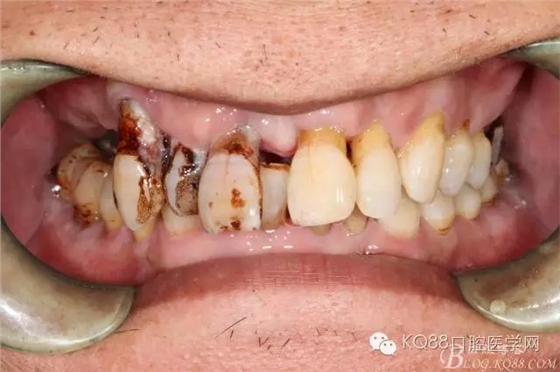

檢查:11、12、13Ⅲ度松動,牙齦退縮,根面暴露,14、15、16、17缺失,余牙不同程度牙齦退縮。

診斷:牙列缺損 牙周炎